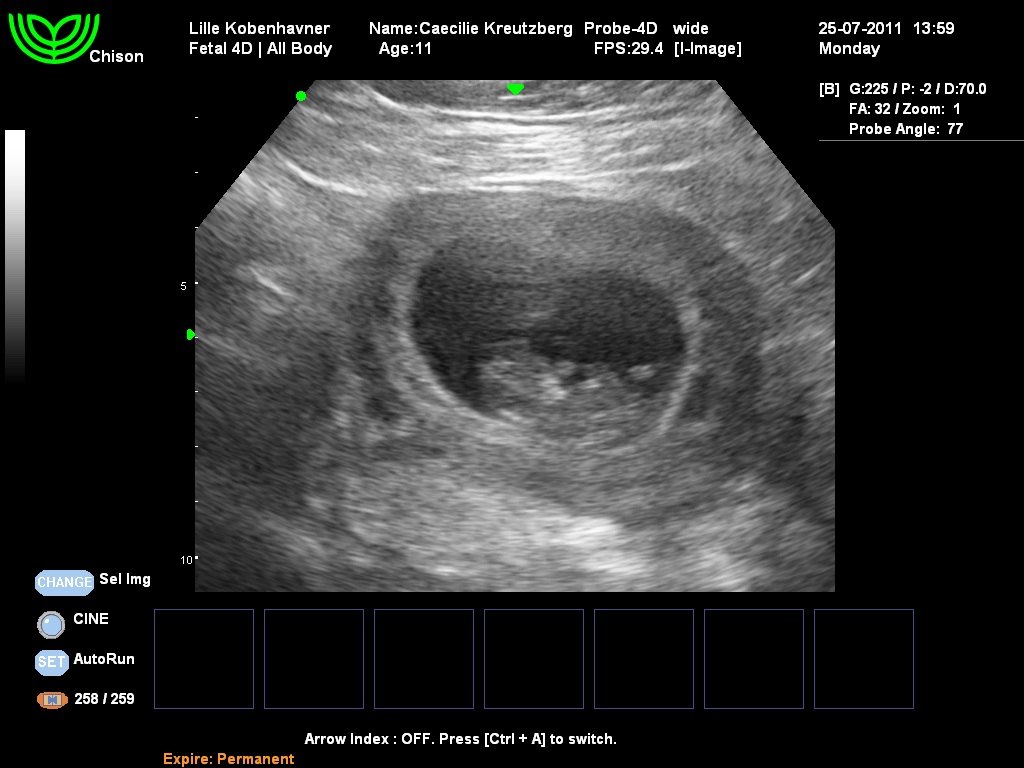

Jeg var til endnu en tryghedsscanning inden vi tog tilbage til Dubai, og puha hvor var baby vokset. Den lå endda og vinkede ud til os  Jeg er så glad, og elsker allerede det lille my i maven!

Vedhæftede fotos (klik for at se i fuld størrelse)